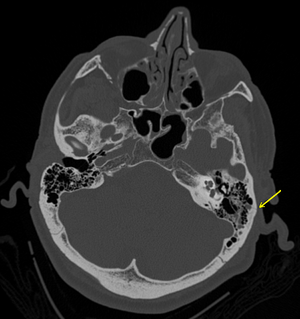

A subtle temporal bone fracture as seen on CT in a person with a severe head injury | |

A basilar skull fracture (or basal skull fracture) is a fracture of the base of the skull, typically involving the temporal bone, occipital bone, sphenoid bone, and/or ethmoid bone.